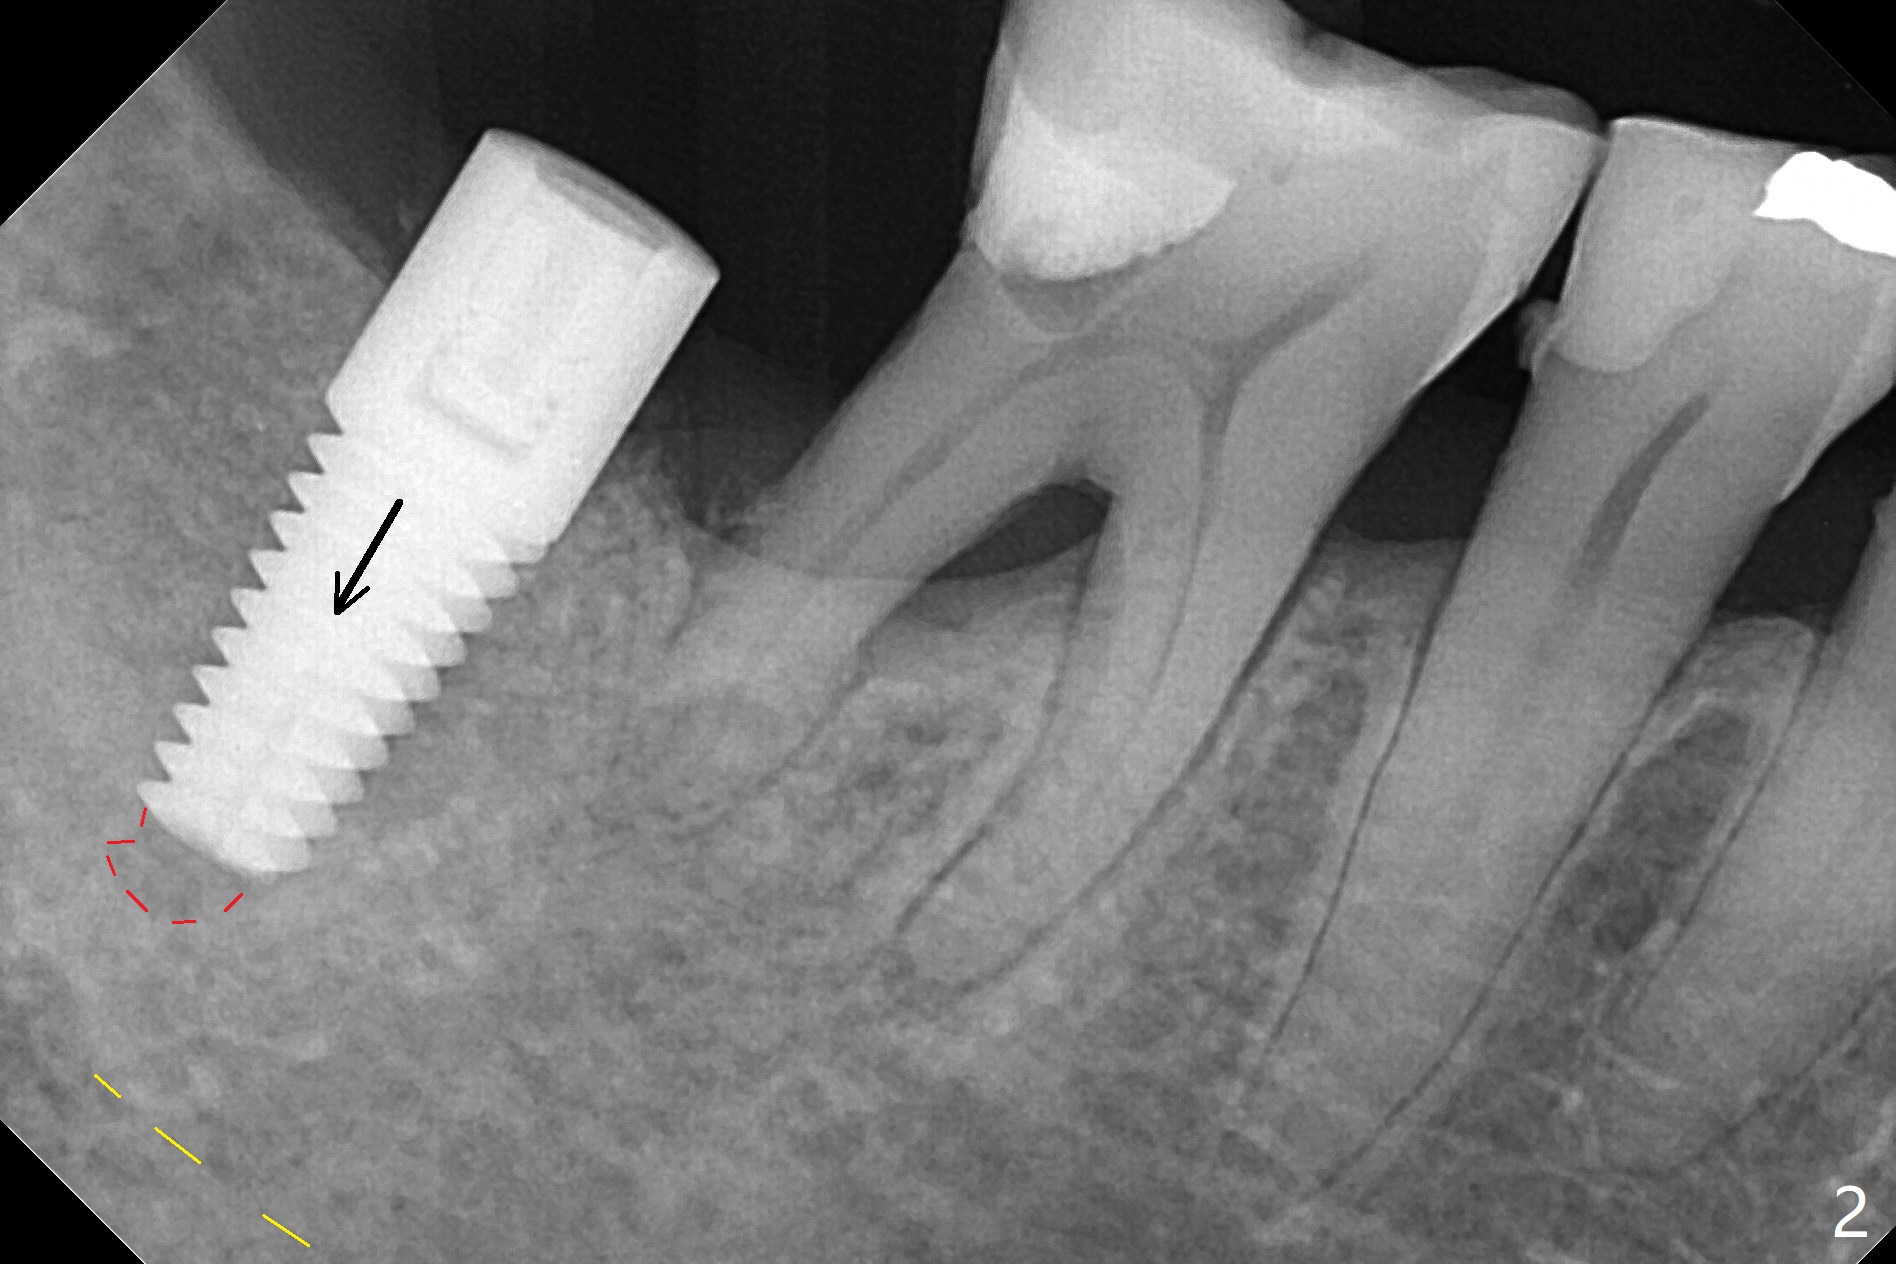

59岁女,吃素,右下7拔除植骨(使用血小板因子),术后7个月证实颊侧骨板再生,但是骨质密度低,导板取模后,家庭医生诊断骨质疏松症,开始服用钙片和Fossamax,后者每周一次,已经四周了。今天她回来植牙(术后10个月),术前决定使用小号钻头,术中的确发现骨质疏松,几乎没有骨削。4毫米钻头完成钻洞,4.5毫米报废植体没有什么稳定性,5毫米植体植入(部分徒手)扭力~45 Ncm(图一(红虚线:根尖钻洞;黄虚线:下齿槽管)),最后将植体种深些(图二:箭头)。